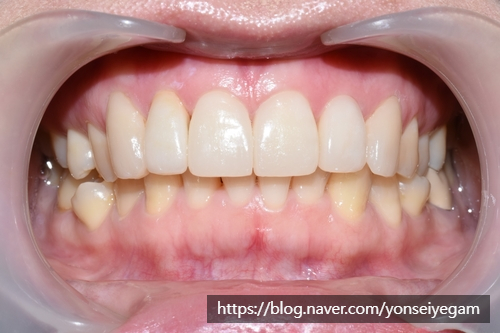

![[시청역/광화문/서대문]삐뚤삐뚤한 치아 무삭제라미네이트로 치아성형 관련 이미지 1](https://pub-9f2bb3498faf4d1d8714b41df24753e3.r2.dev/content/clinics/archive/rseeanjxfu/naver_blog/yonseiyegam/assets/by_hash/3093adbf269d3c6c97887fdfa13a93d2694e97a88cc3e0dcf95457b2c7f54c4b.png)

이번에도 환자분이 사진 공개에 동의한 케이스입니다.

윗니 라미네이트5개와 크라운 전후 입니다.

윗니 라미네이트5개와 굉장히 많이 튀어나온 치아 1개 크라운으로 자연스럽고 고른 치아가 되었습니다.